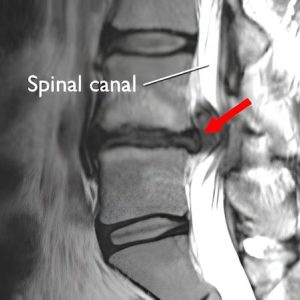

تنگی کانال نخاعی

تنگی کانال نخاعی وضعیتی است که با باریک شدن کانال نخاعی مشخص می شود که می تواند بر طناب نخاعی و اعصاب فشار وارد کند. این باریک شدن می تواند ناشی از عوامل مختلفی از جمله آرتروز ستون فقرات، فتق دیسک و ضخیم شدن رباط های ستون فقرات باشد. علائم تنگی کانال نخاعی ممکن است شامل درد، بی حسی، گزگز و ضعف در پشت، پاها و بازوها باشد و با فعالیت یا ایستادن یا نشستن طولانی مدت بدتر شود.

علائم تنگی کانال نخاعی کمر معمولاً شامل کمردرد و دردی است که از باسن شروع شده و به سمت پایین ساق پا کشیده می‌شود و گاهی تا کف پا ادامه می‌یابد. این درد اغلب با ایستادن طولانی، راه رفتن یا حرکت در مسیرهای سراشیبی تشدید می‌شود، اما با خم شدن به جلو، راه رفتن در سربالایی یا نشستن، کاهش پیدا می‌کند. بیماران همچنین ممکن است احساس سنگینی، ضعف یا خستگی زودرس در پاها را تجربه کنند که می‌تواند بر توانایی انجام فعالیت‌های روزمره تأثیر بگذارد.

اوزون می تواند به مانند یک استروئید جایگزین بهتر عمل کند، زیرا مکانیسم اثر مشابهی دارد در حالی که داروی بسیار ایمن تری است. درد عصبی در تنگی کانال نخاعی را می توان با میکروسیرکولاسیونی که اوزون القا می کند بهبود بخشید.